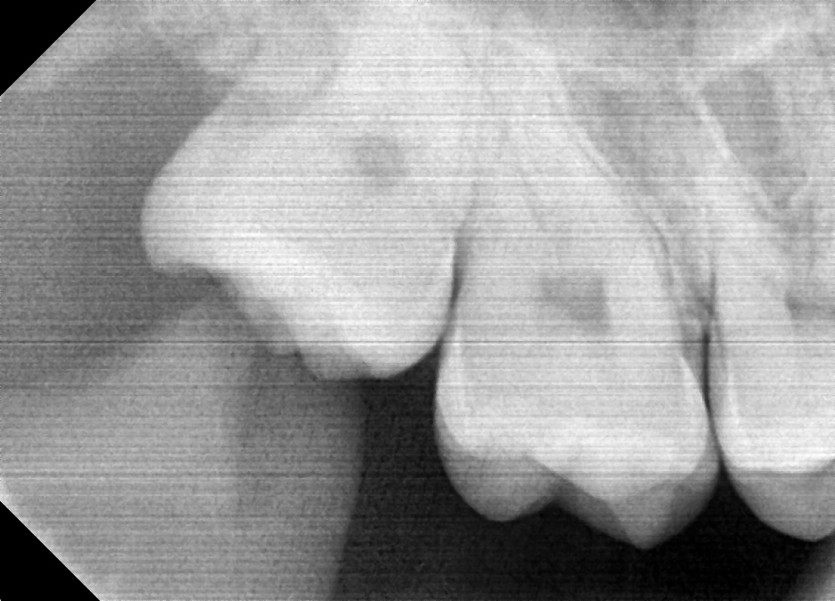

#18,48 사랑니 발치

구강외과 전문의가 당일 발치했습니다.